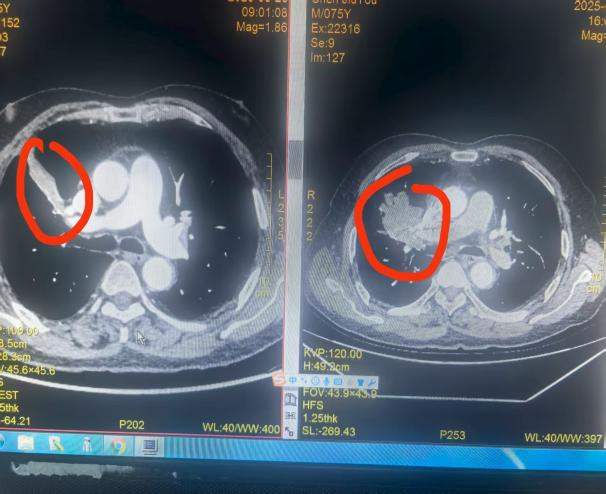

然而,桂林医科大学第二附属医院胸心血管外科专家团队并未放弃。他们联合呼吸科、放疗科、肿瘤科等开展多学科诊疗(MDT),制定了"新辅助免疫联合化疗"方案。经过 4 个月治疗,复查显示原发灶从"橙子"大小缩小到"鹌鹑蛋"大小,纵膈淋巴结明显缩小。多学科团队评估后认为:"现在可以手术了!"

如今,他们复查 CT 片上残余的阴影,恰似生命韧性的勋章。